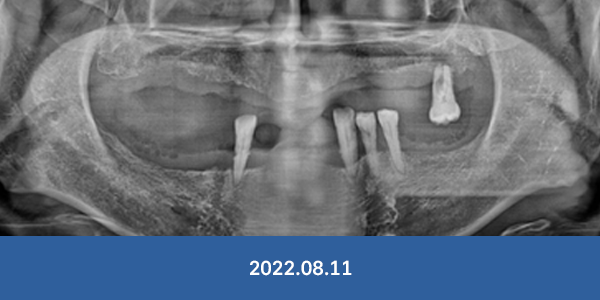

이정웅 대표원장

임플란트 식립 개수

연간 3천개

최근 6년 임플란트 식립개수 누적 1만3천개 돌파

임플란트 수술, 경험이 곧 실력입니다.

임플란트 부작용, 더는 걱정마세요!

개원 이래 대학병원 전원율 0% 달성

※ 서울감동치과에서 실제 수술 받으신 환자분들의 사진입니다.